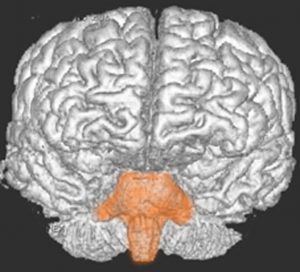

- 脳の底面からしか見えないのでいろいろな角度から見ています

これは脳の中心部を縦切りにした写真です。脳幹部は上から順に,中脳 midbrain (黄色),橋 pons(オレンジ),延髄 medulla oblongata(ピンク)と呼ばれます。

共通しているのは脳幹部の障害では意識障害が出ることです。中脳脚から延髄腹側まで錐体路という運動神経を司る経路があり,これが障害されると片麻痺や四肢麻痺がでます。脊髄視床路の障害では全身の感覚障害となります。主として背側損傷では運動失調も出ます。脳神経麻痺,眼球運動障害,嘔吐などさまざまで複雑な症候が出る重要な部位です。